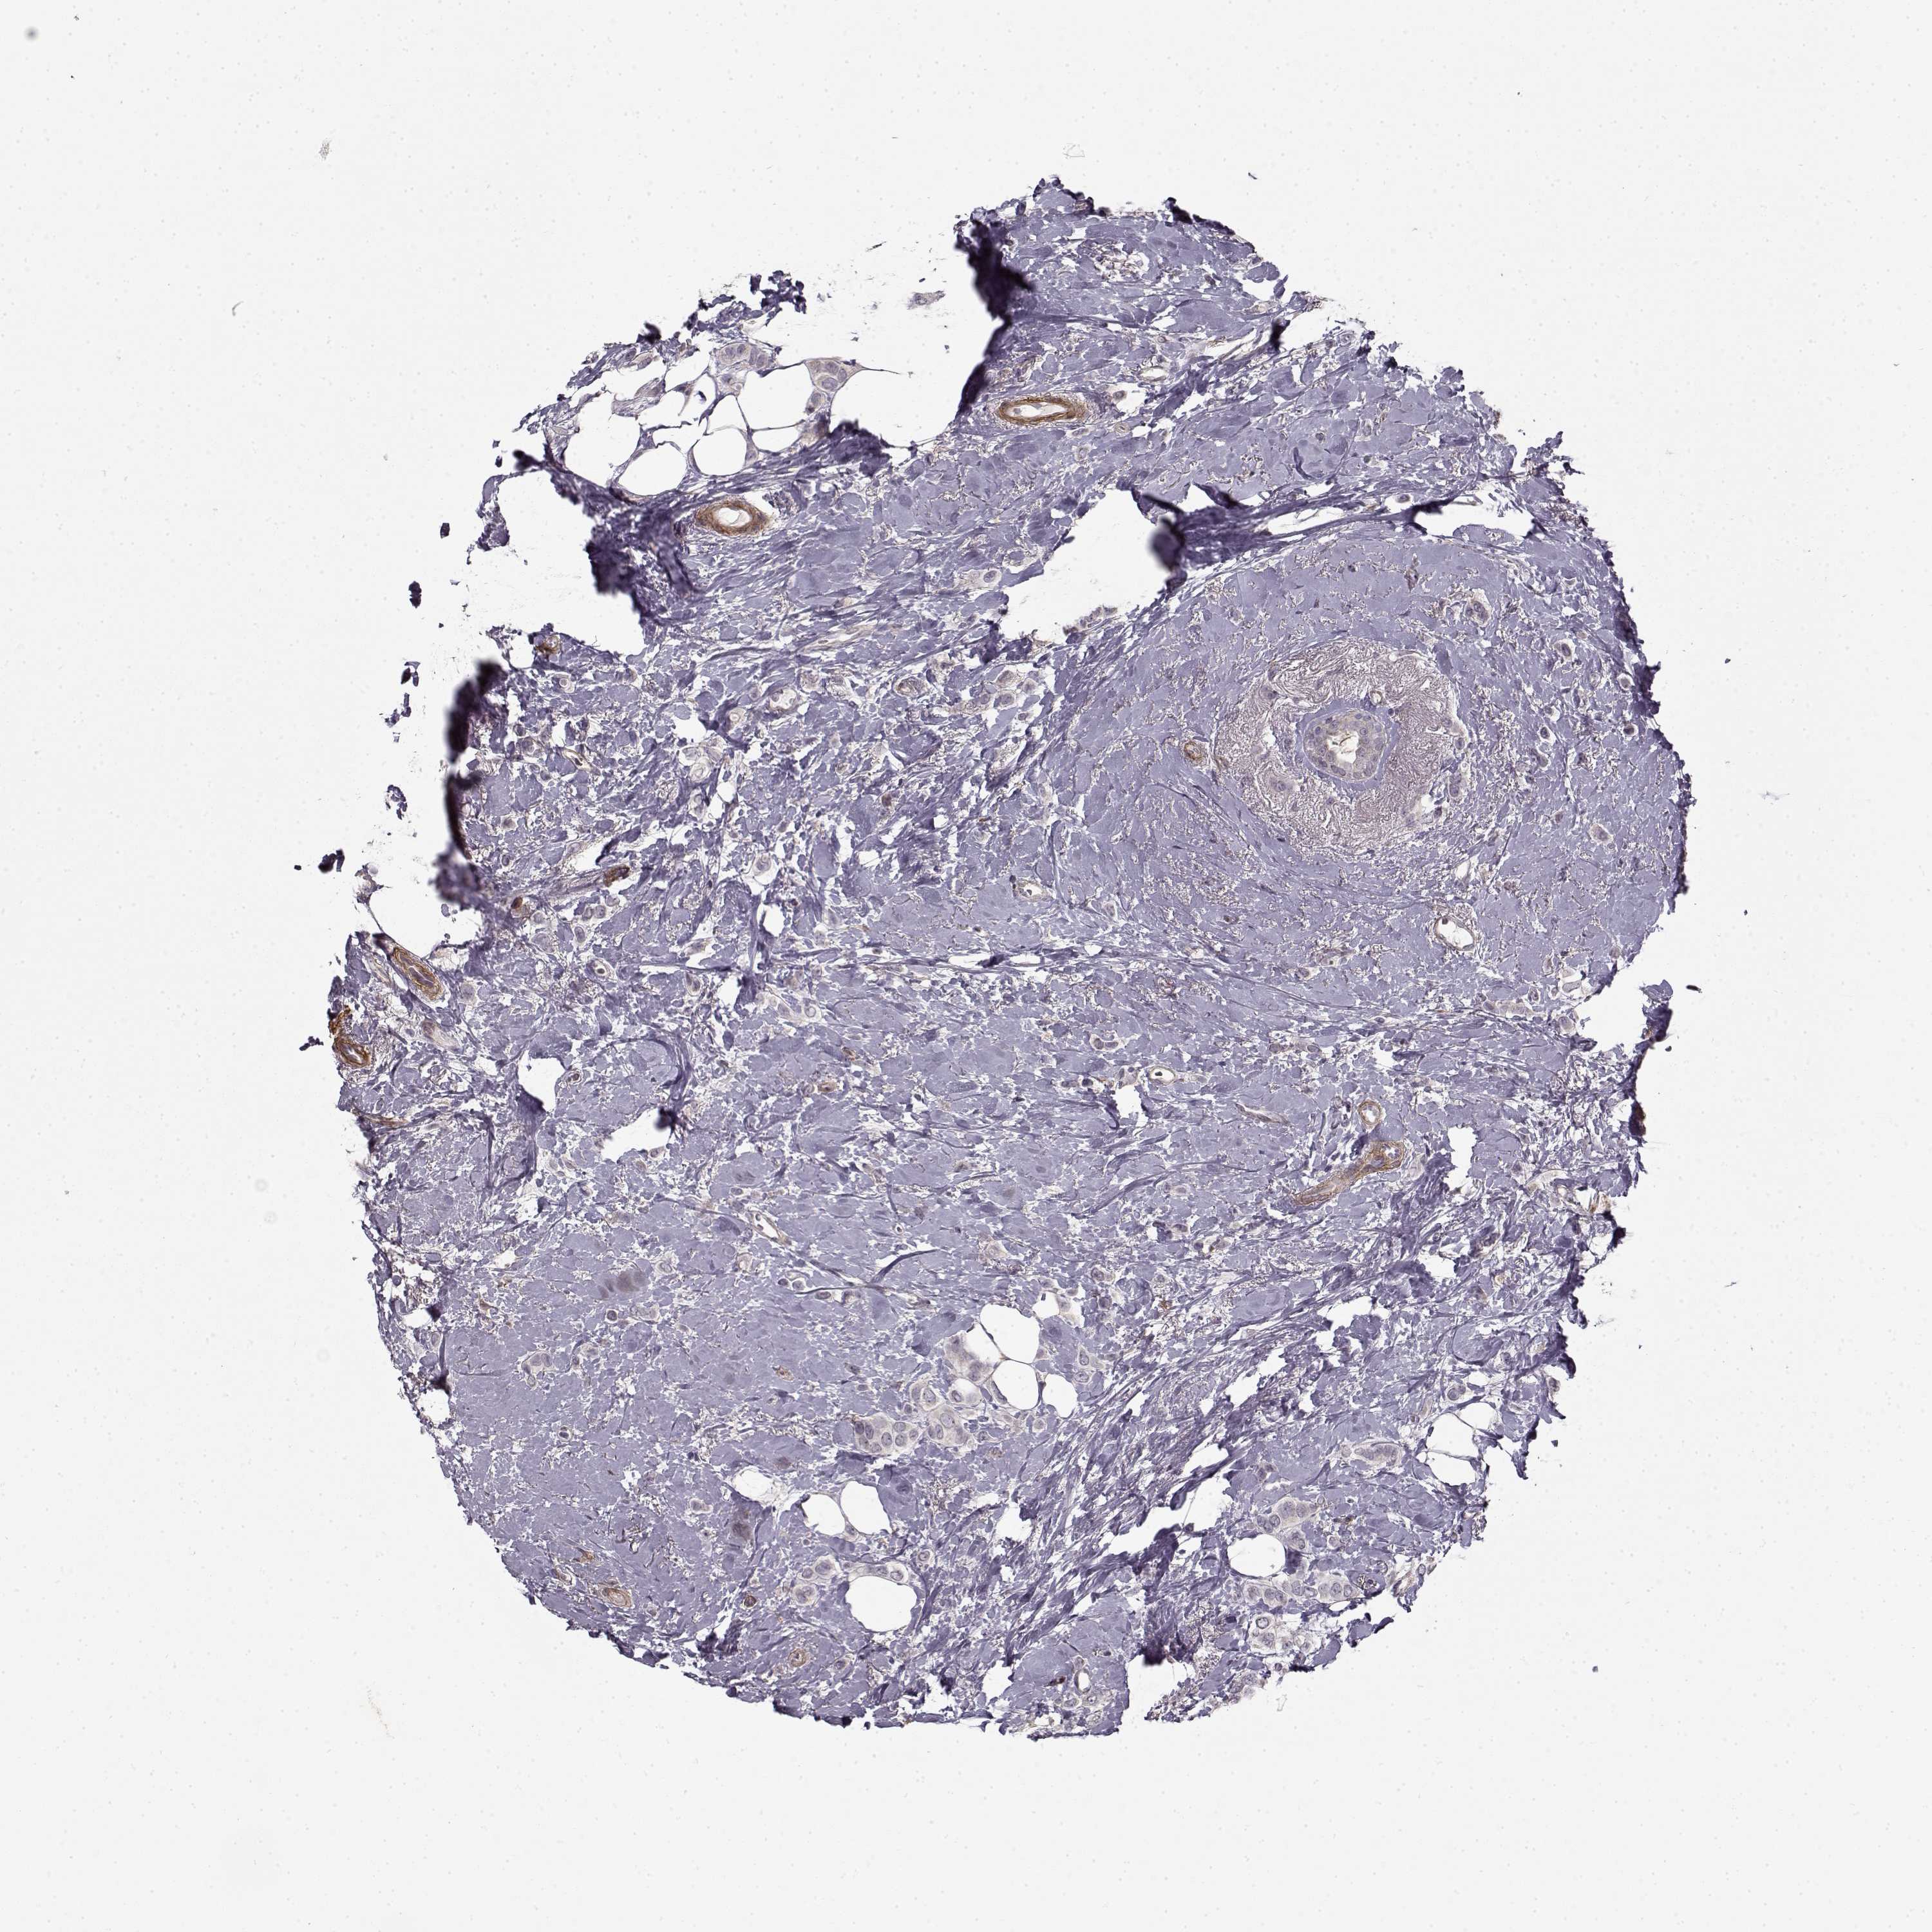

CANCER BREAST CANCER Show tissue menu

BRCA TCGA BRCA VALIDATION PROTEIN EXPRESSION

ANTIBODIES

AND

VALIDATION